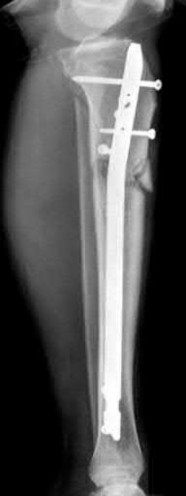

Question 19:

A 28-year-old male sustains a closed comminuted tibial shaft fracture. Two hours post-injury, he develops severe leg pain unyielding to narcotics. His blood pressure is 120/80 mmHg. Intracompartmental pressure monitoring is performed. Based on current guidelines, which measurement dictates an emergent 4-compartment fasciotomy?

Correct Answer: Delta pressure (Diastolic BP - Compartment Pressure) < 30 mmHg

Explanation:

Acute compartment syndrome is classically defined by tissue hypoperfusion. The absolute compartment pressure is less reliable than the differential pressure (Delta P). A Delta P (Diastolic Blood Pressure minus Compartment Pressure) of less than 30 mmHg is an absolute indication for emergency fasciotomy, as capillary perfusion gradient is lost when tissue pressure approaches the diastolic pressure.